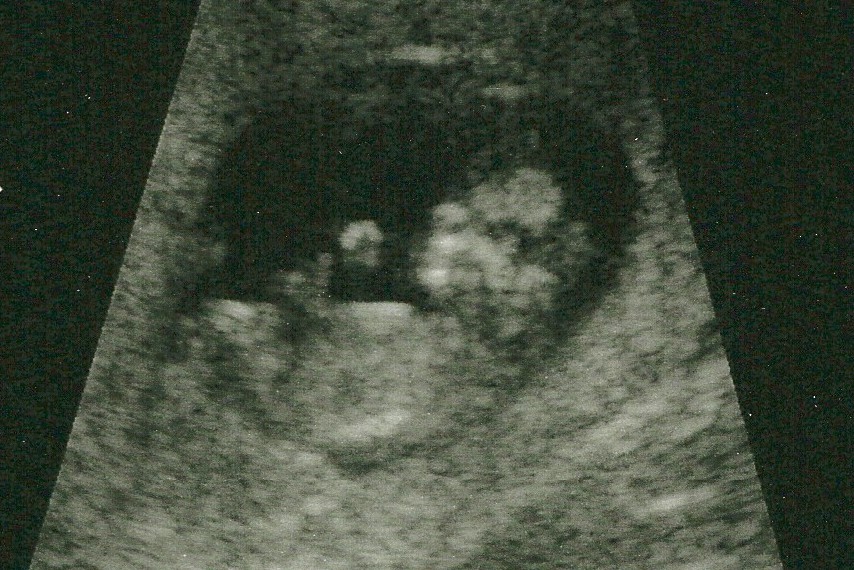

The womb isn’t quite as secluded as it used to be. Now we get to see some of the knitting as God displays his workmanship in creating another human being – awesome!